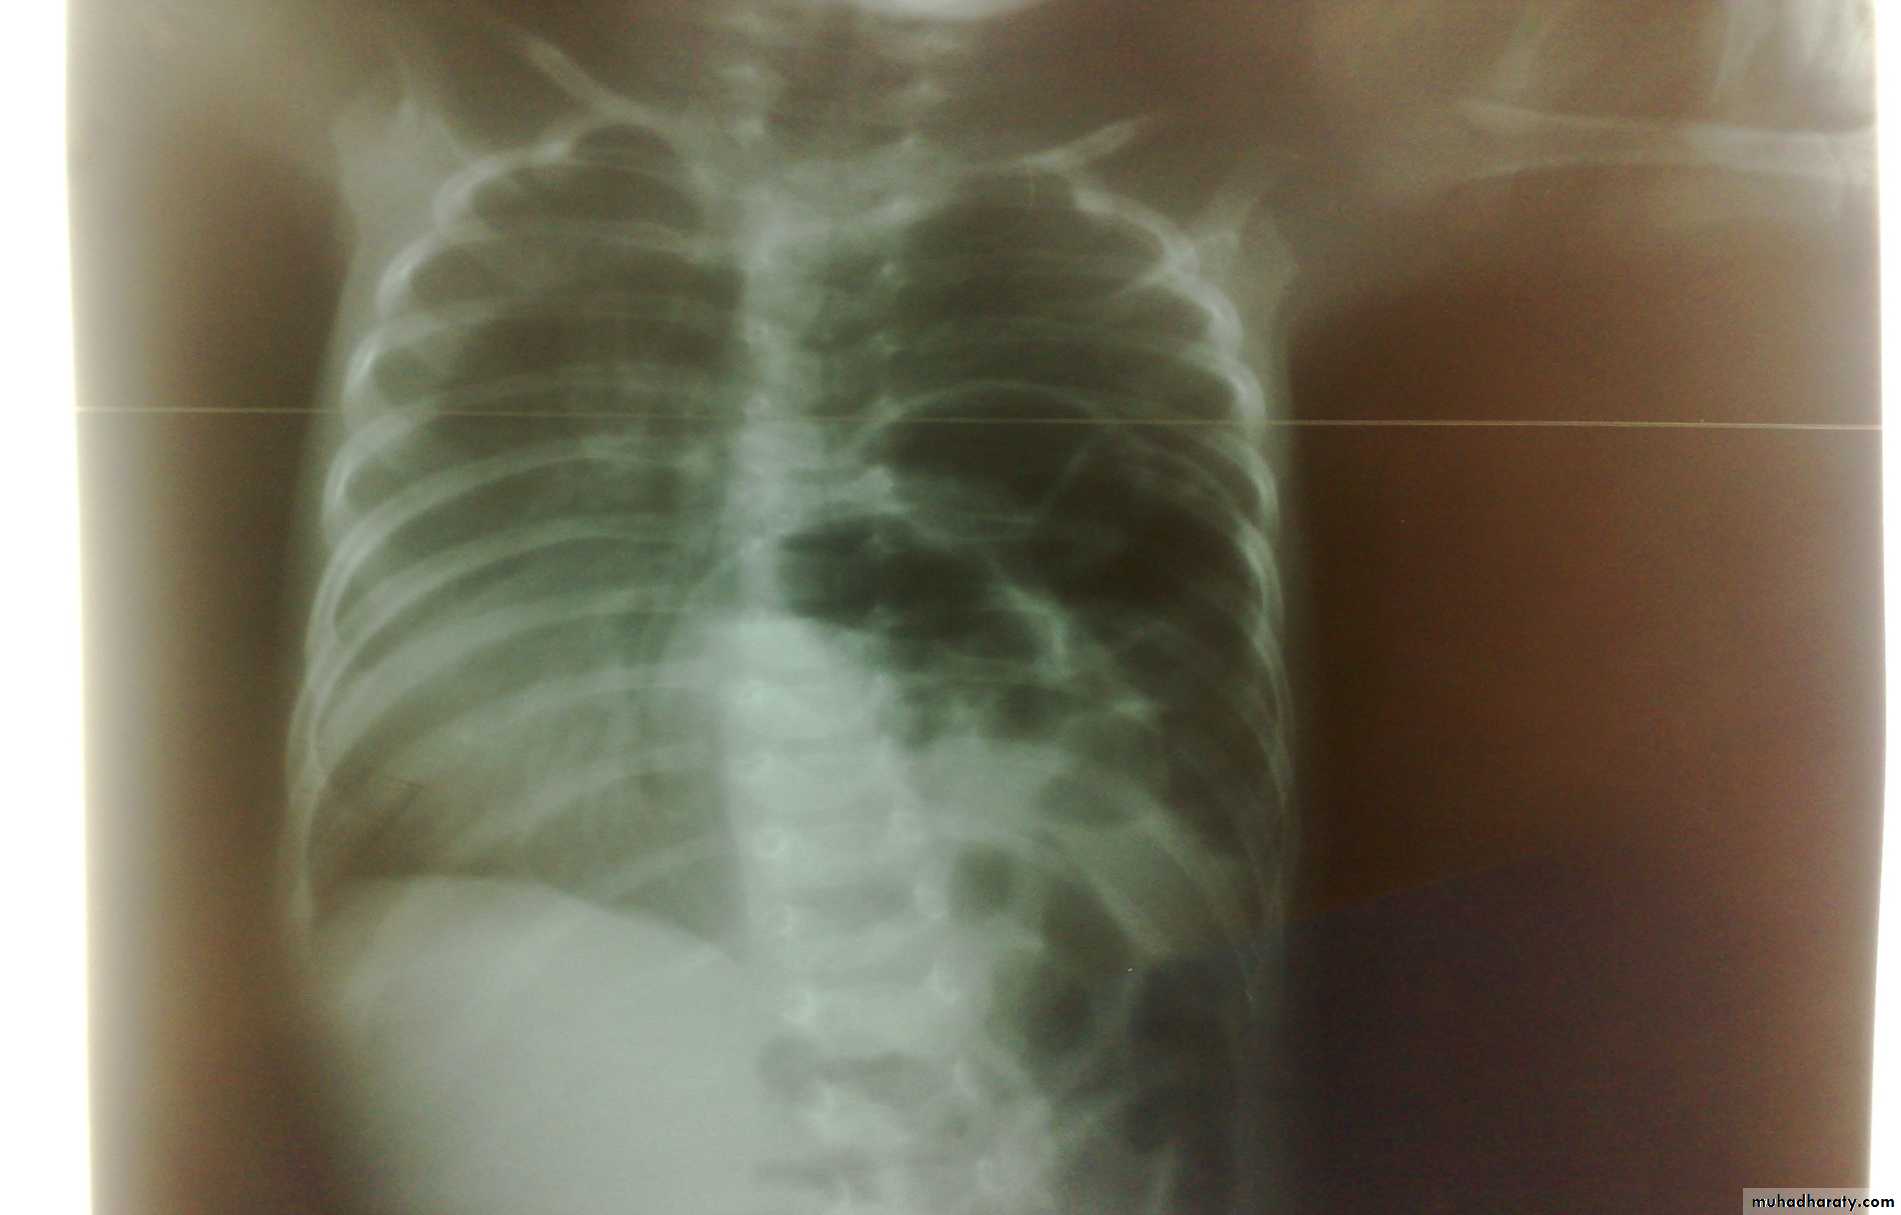

Respiratory Distress in the NewbornFirst photo:

Diagnosis: eventration of diaphragmDescription: mild dextrocardia – recurrent chest infection – diaphragm is present

mild distress - 7 months age baby – less number of intestinal loops in the chest

there is lung tissue in the chest - Paradoxical movement of the diaphragm.

Treatment: plication of the hemi-diaphragm (through thoracic approach).